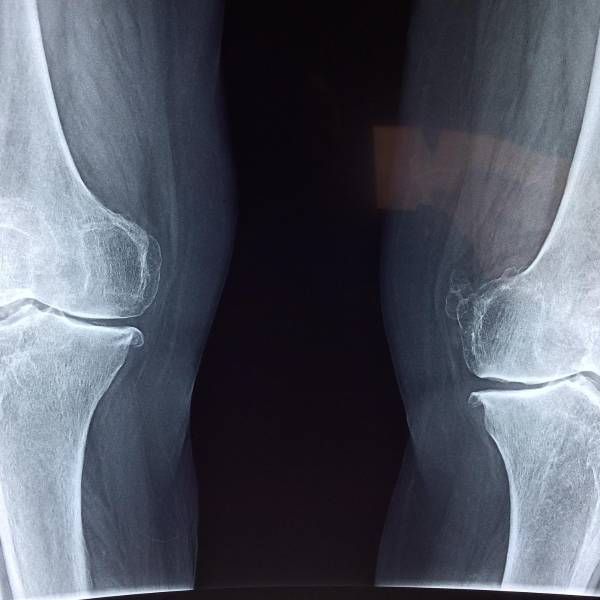

Esto provoca el infradiagnóstico de cefaleas causadas por problemas en las cervicales o en la mandíbula, lo que también dificulta identificar la solución a esos síntomas. En este sentido, los fisioterapeutas madrileños han recomendado que, ante un episodio continuado de cefalea, los pacientes consulten también con un fisioterapeuta o traumatólogo para contar con un diagnóstico más completo que permita averiguar si existe alguna patología relacionada con los huesos que pueda ser la causa o un agravante del problema.

Un dolor de cabeza causado por afecciones cervicales o mandibulares puede producir síntomas similares a la migraña, con o sin aura, y a la cefalea tensional, e incluso pueden coexistir ambos problemas y ser abordados solamente con medicación. Si eso ocurre, se estará tratando de manera no exitosa.

De ahí la importancia de contar con una valoración adicional a la neurológica y, sobre todo, de pautar un tratamiento que también tenga en cuenta, a través de la fisioterapia, la necesaria mejora de los problemas cervicales o relacionados con huesos y articulaciones involucrados en el problema. "La fisioterapia, además, puede ayudar a mejorar la higiene postural y a prevenir, con ello, episodios futuros de cefaleas, por lo que se recomienda incorporar un enfoque terapéutico al tratar el dolor de cabeza", han zanjado.